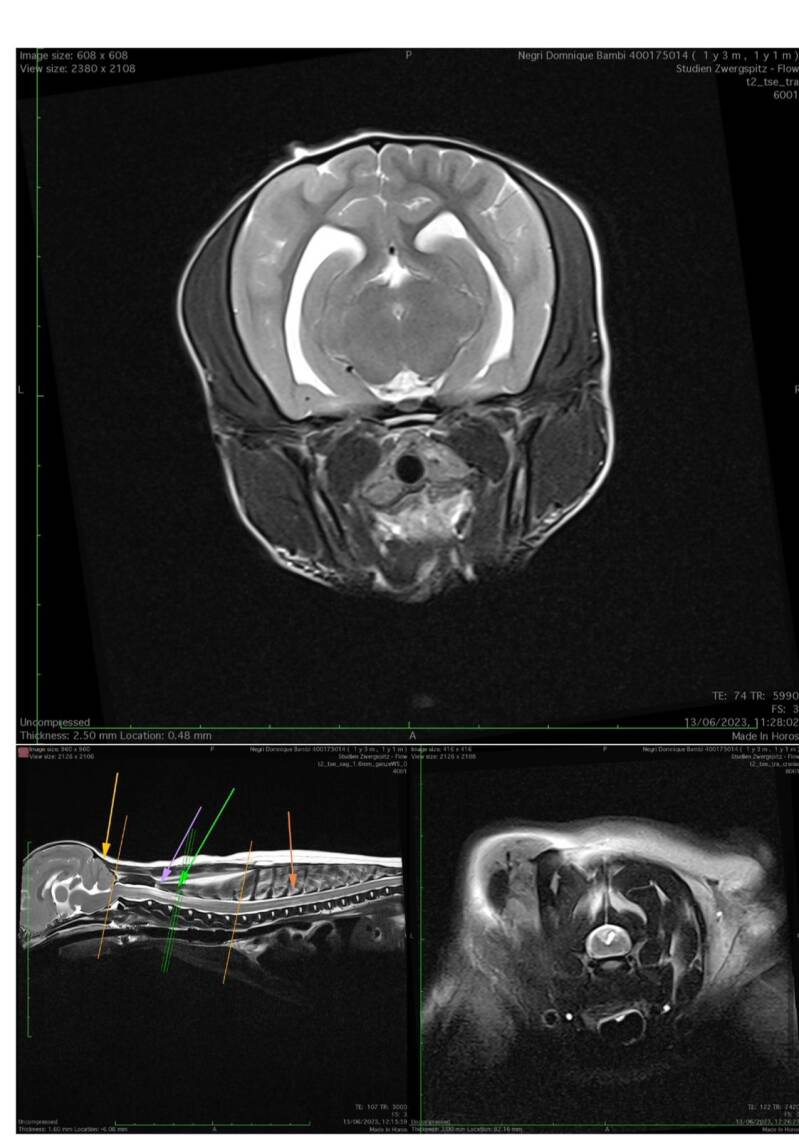

Ich machte von Bambi ein MRT. Ich war schon sooo gebrannt mit all diesen Krankheiten, dass ich es einfach wissen wollte. Ich dacht.. endlich werde ich Glück haben und einen gesunden Pom gekauft haben.

Bambi hat Cm1 und Sm2 und eine offene Fontanelle.

Ihre Syringomyelie ist schon so weit fortgeschritten, dass diese bereits 54% ihres Rückenmarkes verdrängt hat.